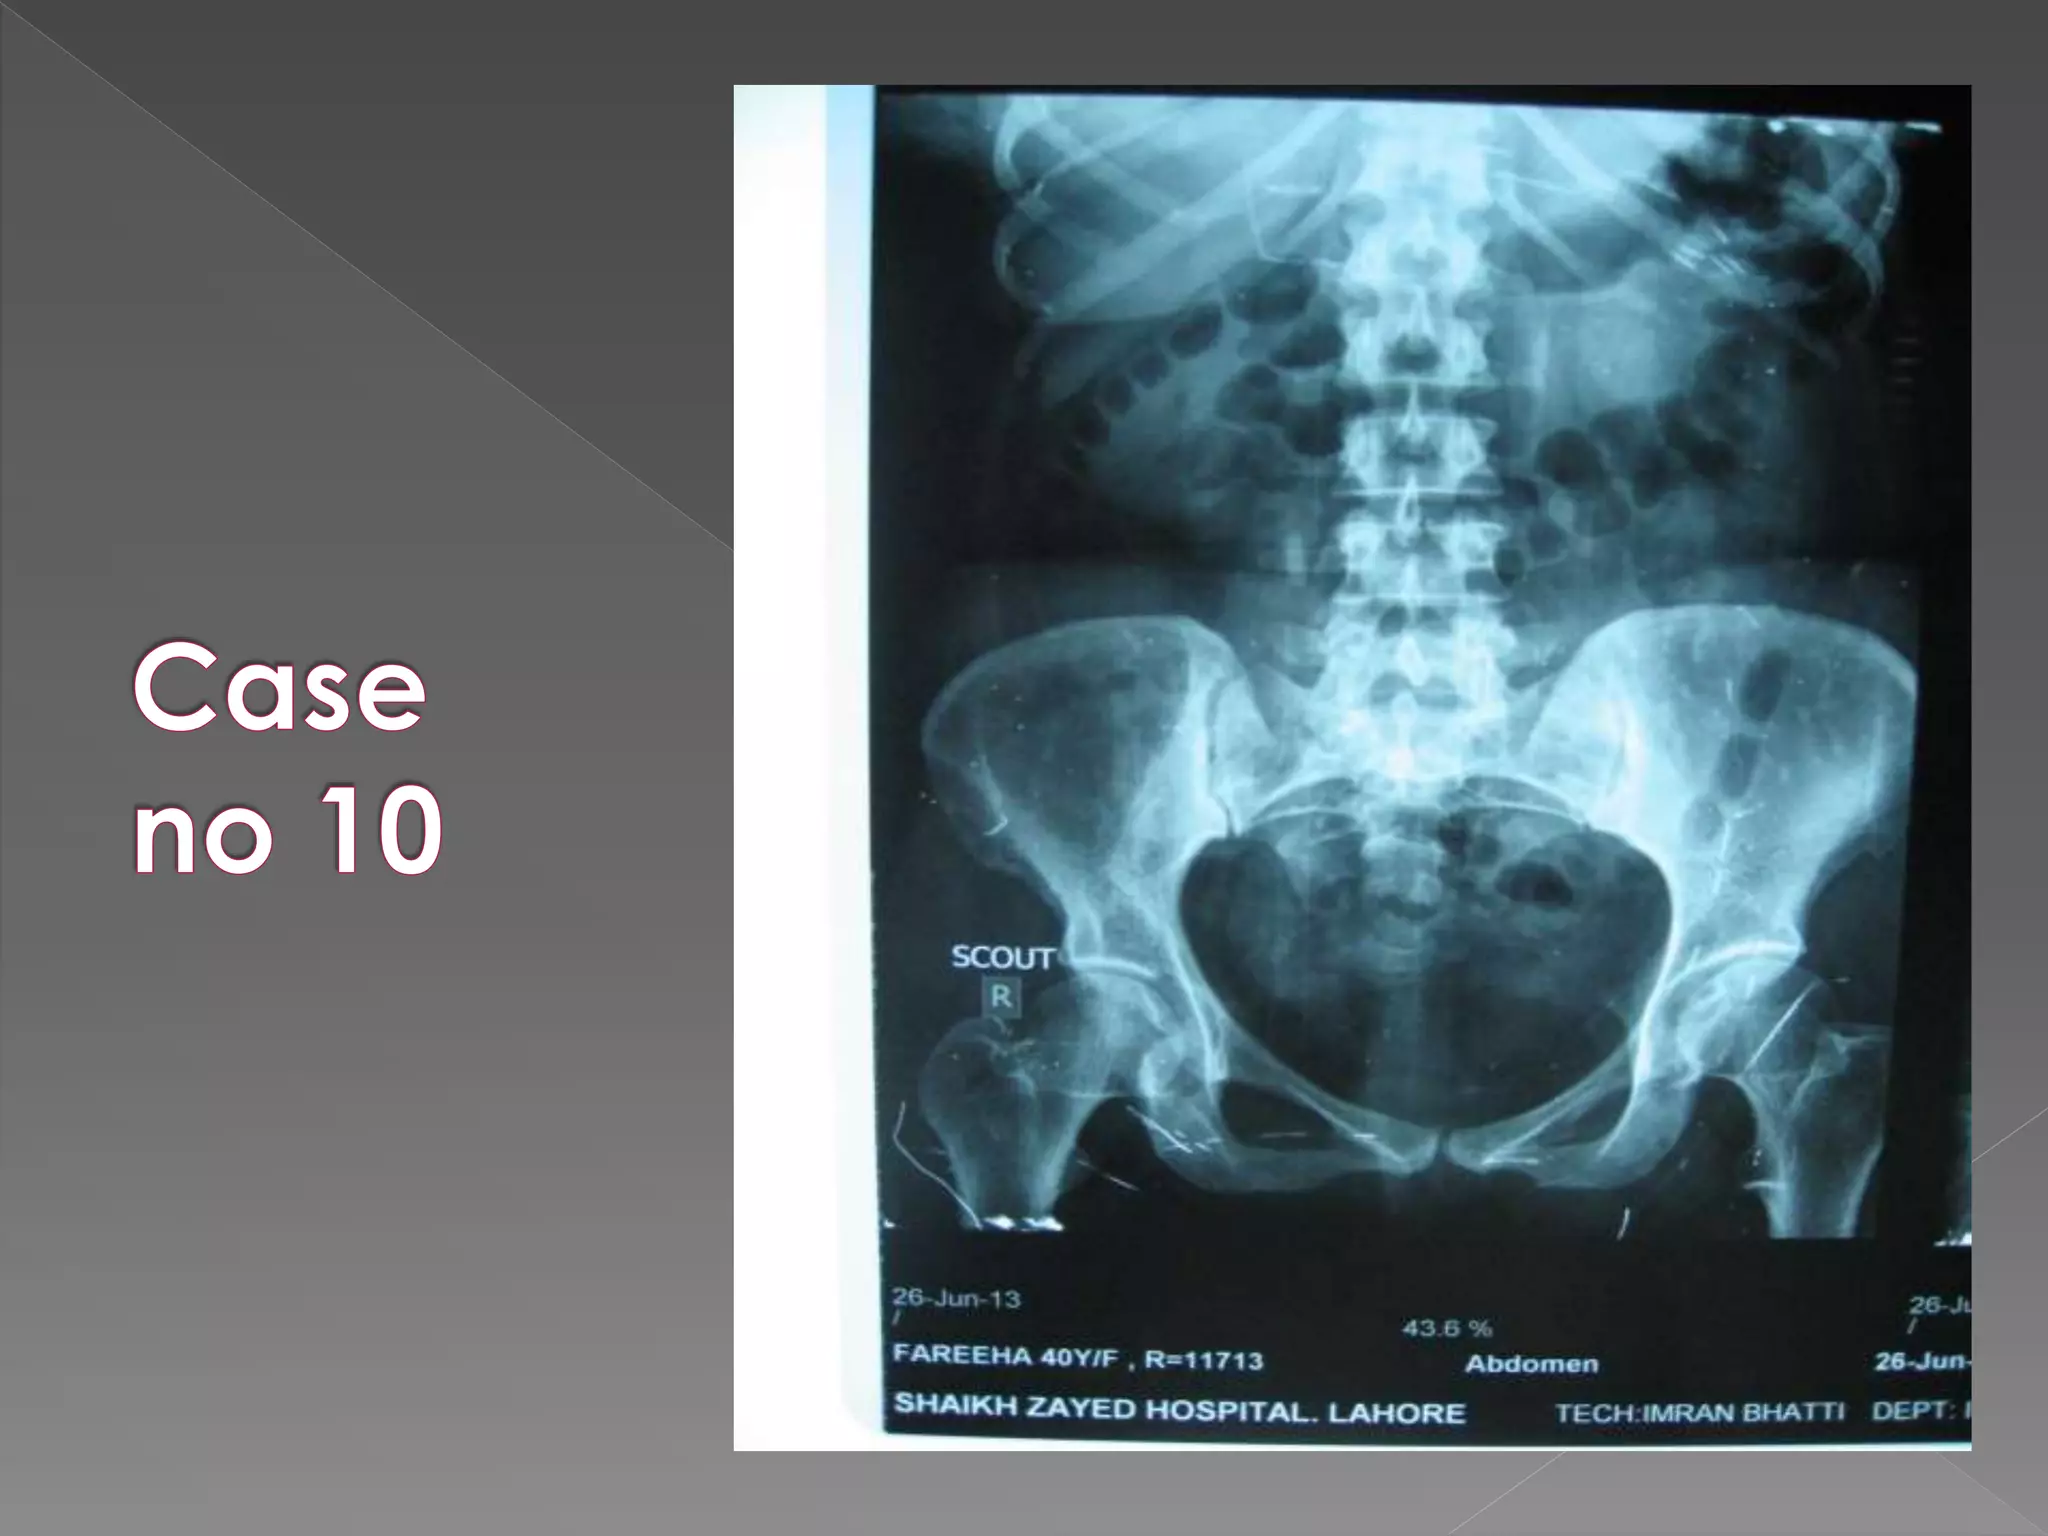

1) Pre contrast film “scout” film. (full length)

1) Pre contrast

X ray films 1)Pre contrast 2) 5 mins 3) 25 mins 4) Post void